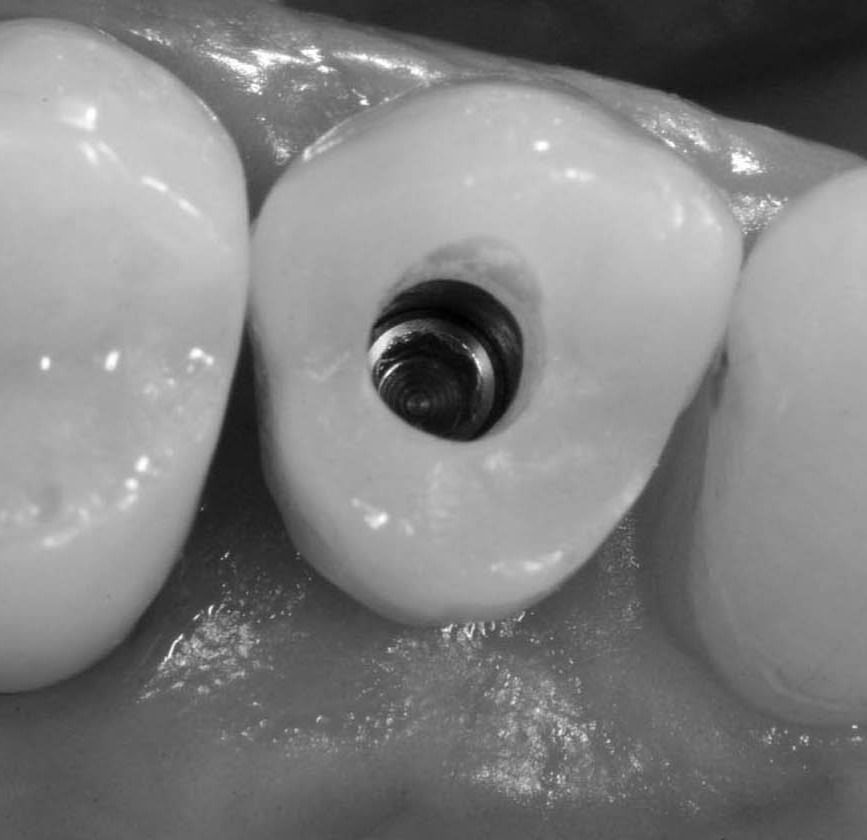

Screw retained temporary crown in resin, made on Prama IN healing abutment, which maintains the same emergence profile and the same closure around the implant neck of the relative healing screw.

Temporary crown in place: occlusal view.